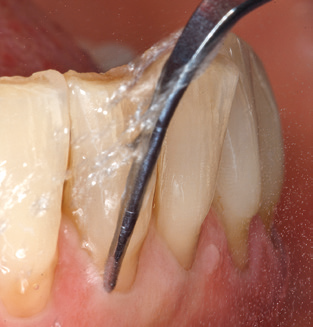

Good illumination of the working field facilitates the process considerably. The system used by the authors achieves this thanks to a 5x LED ring integrated in the handpiece. Naturally, a range of working tips for different indications is also offered. A straight, universally employable tip is the basic instrument required for machine cleaning of natural teeth (Fig. 5a and b). Curved tips, which allow access to exposed furcations, are also available for hard-to-reach areas in the posterior region (Fig. 6).

Following machine cleaning of the tooth and implant surfaces, the surfaces of the natural teeth are cleaned manually using standard hand instruments. When performing manual cleaning, particular attention must be given to maintaining the correct angle of application, appropriate sharpness, good support and working with the curette from apical to coronal. Either titanium or carbon curettes should be used for post-cleaning of the implant structures (Fig. 8). In addition to the use of ultrasonic devices, power jet devices can also be used in conservative dentistry. However, it must be taken into consideration that these procedures are not suitable for removing hard deposits and thus they cannot replace the use of hand instruments and ultrasonic instruments completely. In all cases, cleaning is followed by mechanical polishing of the accessible tooth and implant surfaces with polishing cups and polishing compounds (Fig. 9).

Fig. 4: Flexible probes with millimetre markings are recommended for the probing of dental implants (e.g. Colorvue Kit PCV11KIT6, Hu­Friedy). – Fig. 5a and b: A straight working tip (1P, W&H Dentalwerk Bürmoos GmbH) is a suitable instrument for use on all natural teeth. – Fig. 6: Curved working tips (3Pr/3Pl, W&H Dentalwerk Bürmoos GmbH) lend themselves to the processing of difficult-to-reach areas of the tooth and root surfaces (e.g. furcations). – Fig. 7: The tapered, hexagonal implant cleaning tip (1I, W&H Dentalwerk Bürmoos GmbH) permits atraumatic and efficient cleaning of the crown and abutment surfaces. – Fig. 8: Titanium and carbon curettes are suitable instruments for the manual cleaning of the implant surfaces.